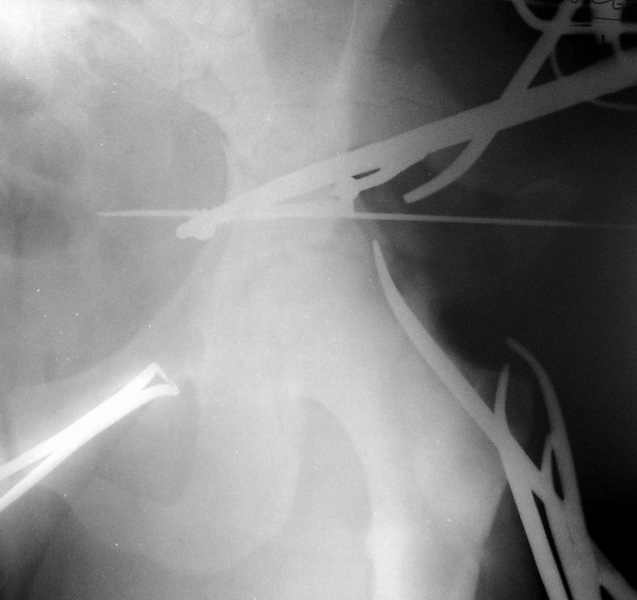

Сегодня на приеме был пациент, чьи начальный снимок напомнил обсуждаемый сейчас (см. выше). Снимки в других проекциях, показывающие истинный характер повреждения, ниже. Это inlet проекция (вход в таз) и запирательная проекция Judet.

Травма 17 ноября 2002 г., поступил к нам 1 декабря, оперирован 8-го - открытая репозиция, остеосинтез пластинками и винтами. Учитывая повреждение переднего полукольца справа, и крестца и крестцово-подвздошного сочленения слева, наложили аппарат на 2 месяца.

Для экономии места привожу интра- и послеоперационный обзорный снимок, без дополнительных проекций.